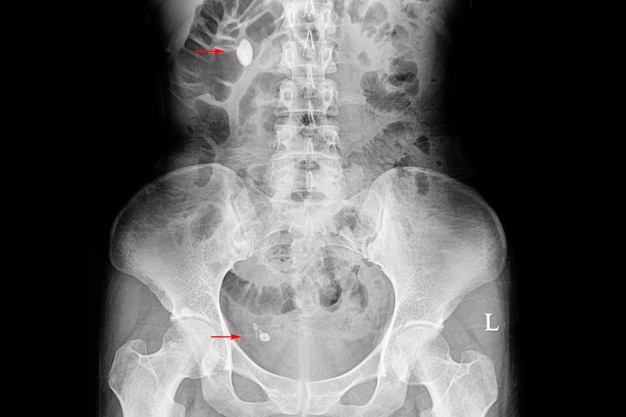

요로결석 증상으로 갑작스럽게 옆구리의 심한 통증, 남자의 경우 아랫배, 고환, 음낭으로 뻗치는 통증, 구역질, 구토, 배가 빵빵한 느낌, 피가 섞인 오줌 등 요로결석 증상이 나타날때쯤이면 심한 고통으로 인해 응급실을 가야할 정도로 극악의 고통을 느끼게 된다. 요로결석은 통증이 심하고 갑작스럽게 요로결석 증상이 나타나면 몸을 가눌 수 도 없게 된다.

요로결석의 치료는 결석의 위치와 크기에 따라 달라지는데 보통 결석의 자연적인 배출을 유도하는 자연대기요법, 체외충격파쇄석술 같은 비수술적 치료와 수술적 치료로 구분된다. 결석의 크기가 4mm 이하일 경우 수분 섭취와 약물 치료 등으로 환자의 60~80%는 자연배출을 기대해 볼 수 있다. 만약 자연배출이 되지 않을 경우 비수술 치료법인 체외충격파쇄석술을 시행하게 된다. 결석이 커져 요관을 막으면 신장 기능을 저하시키기 때문에 요로결석이 생기는 즉시 제거하는 것이 좋다.